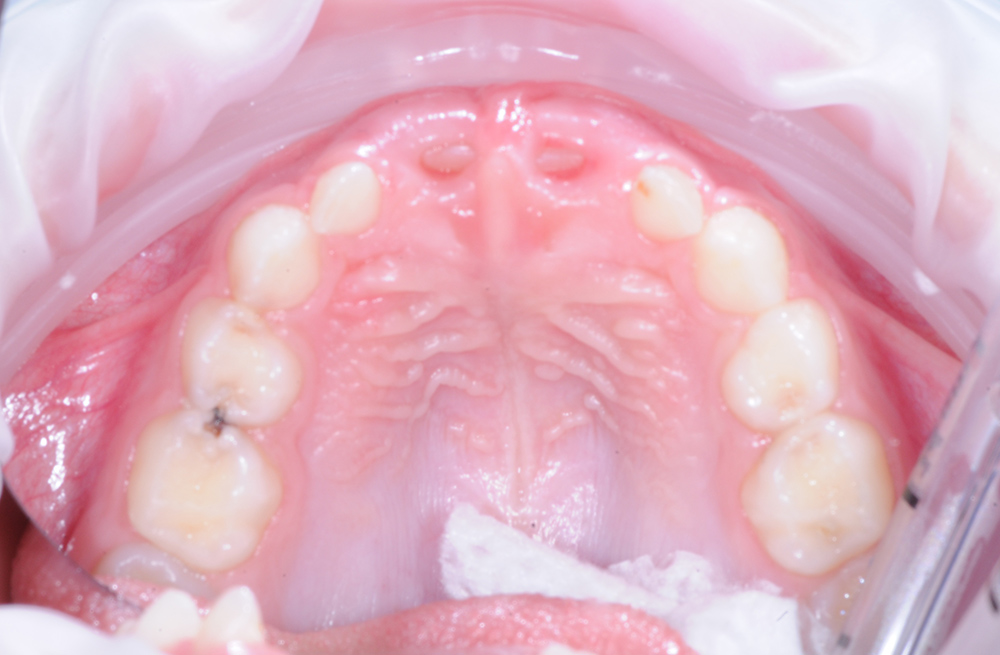

Замена некачественной пломбы и лечение глубокого кариеса перед ортодонтическим лечением